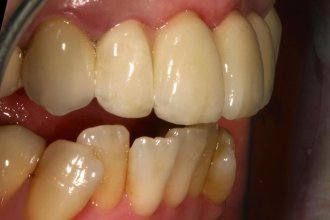

Fotos zur Farbbestimmung, Gesichtsanalyse und Korrekturhilfe